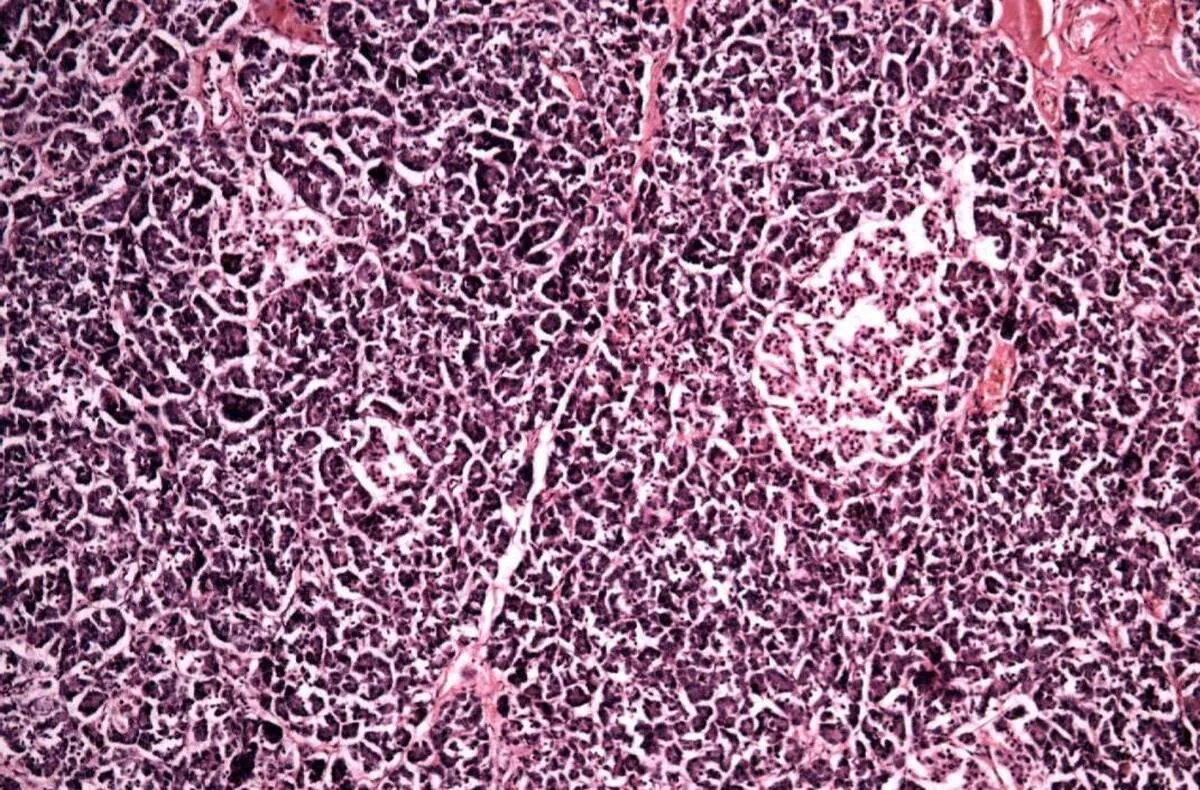

پانکراس از سلول‌های برون‌ریز و غدد درون‌ریز تشکیل شده است. سلول‌های غدد درون‌ریز مواردی هستند که هورمون‌هایی ازجمله انسولین را ترشح می‌کنند و سلول‌های برون‌ریز آنزیم‌هایی می‌سازند که در روده کوچک ترشح می‌شود و به هضم غذا کمک می‌کند. سلول‌های مجرایی (ductal cells) سلول‌های برون‌ریزی بوده که مجاری را پوشش می‌دهند. این مجاری نیز آنزیم‌های پانکراس را انتقال می‌دهند. تحقیقات پیشین نشان داده‌اند که سلول‌های پیش‌ساز مجاری که از سلول‌های بنیادی به وجود می‌آیند، می‌توانند به سلول‌های بتا تولیدکننده انسولین تمایز یابند.

اکنون در یک تحقیق اولیه محققان انستیتو قلب و دیابت بیکر در استرالیا ترکیبی از دارو‌های مصنوعی و طبیعی را برای تحریک سلول‌های پیش‌ساز مجرایی به کار برده‌اند تا آنها را به سلول‌های مشابه بتا تبدیل کنند که قادر به تولید انسولین هستند. محققان از یک مهارکننده مصنوعی به نام EZH۲ استفاده کردند که بیشتر برای درمان سرطان به کار می‌رود. در این تحقیق از تریپتولید که از یک گیاه چینی گرفته شده و دارای خواص ضدالتهابی و ضد سرطانی است نیز استفاده شد.

محققان متوجه شدند ترکیب مهارکننده EZH۲ و تریپتولید قابلیت پیش ساز سلول‌های مجرای انسان را احیا کرده و آنها را فعال می‌کند. به این ترتیب آنها می‌توانند به سلول‌های بتا متمایز شوند. هنگامی‌که این سلول‌ها در معرض محلول گلوکز قرار گرفتند، سلول‌ها انسولین ساختند؛ البته به تحقیقات بیشتری برای بررسی مکانیسم عملکرد این دارو‌ها نیاز است، اما به گفته محققان این پژوهش نشان می‌دهد روش مذکور ظرفیت ایجاد یک درمان جایگزین برای دیابت نوع یک را دارد.